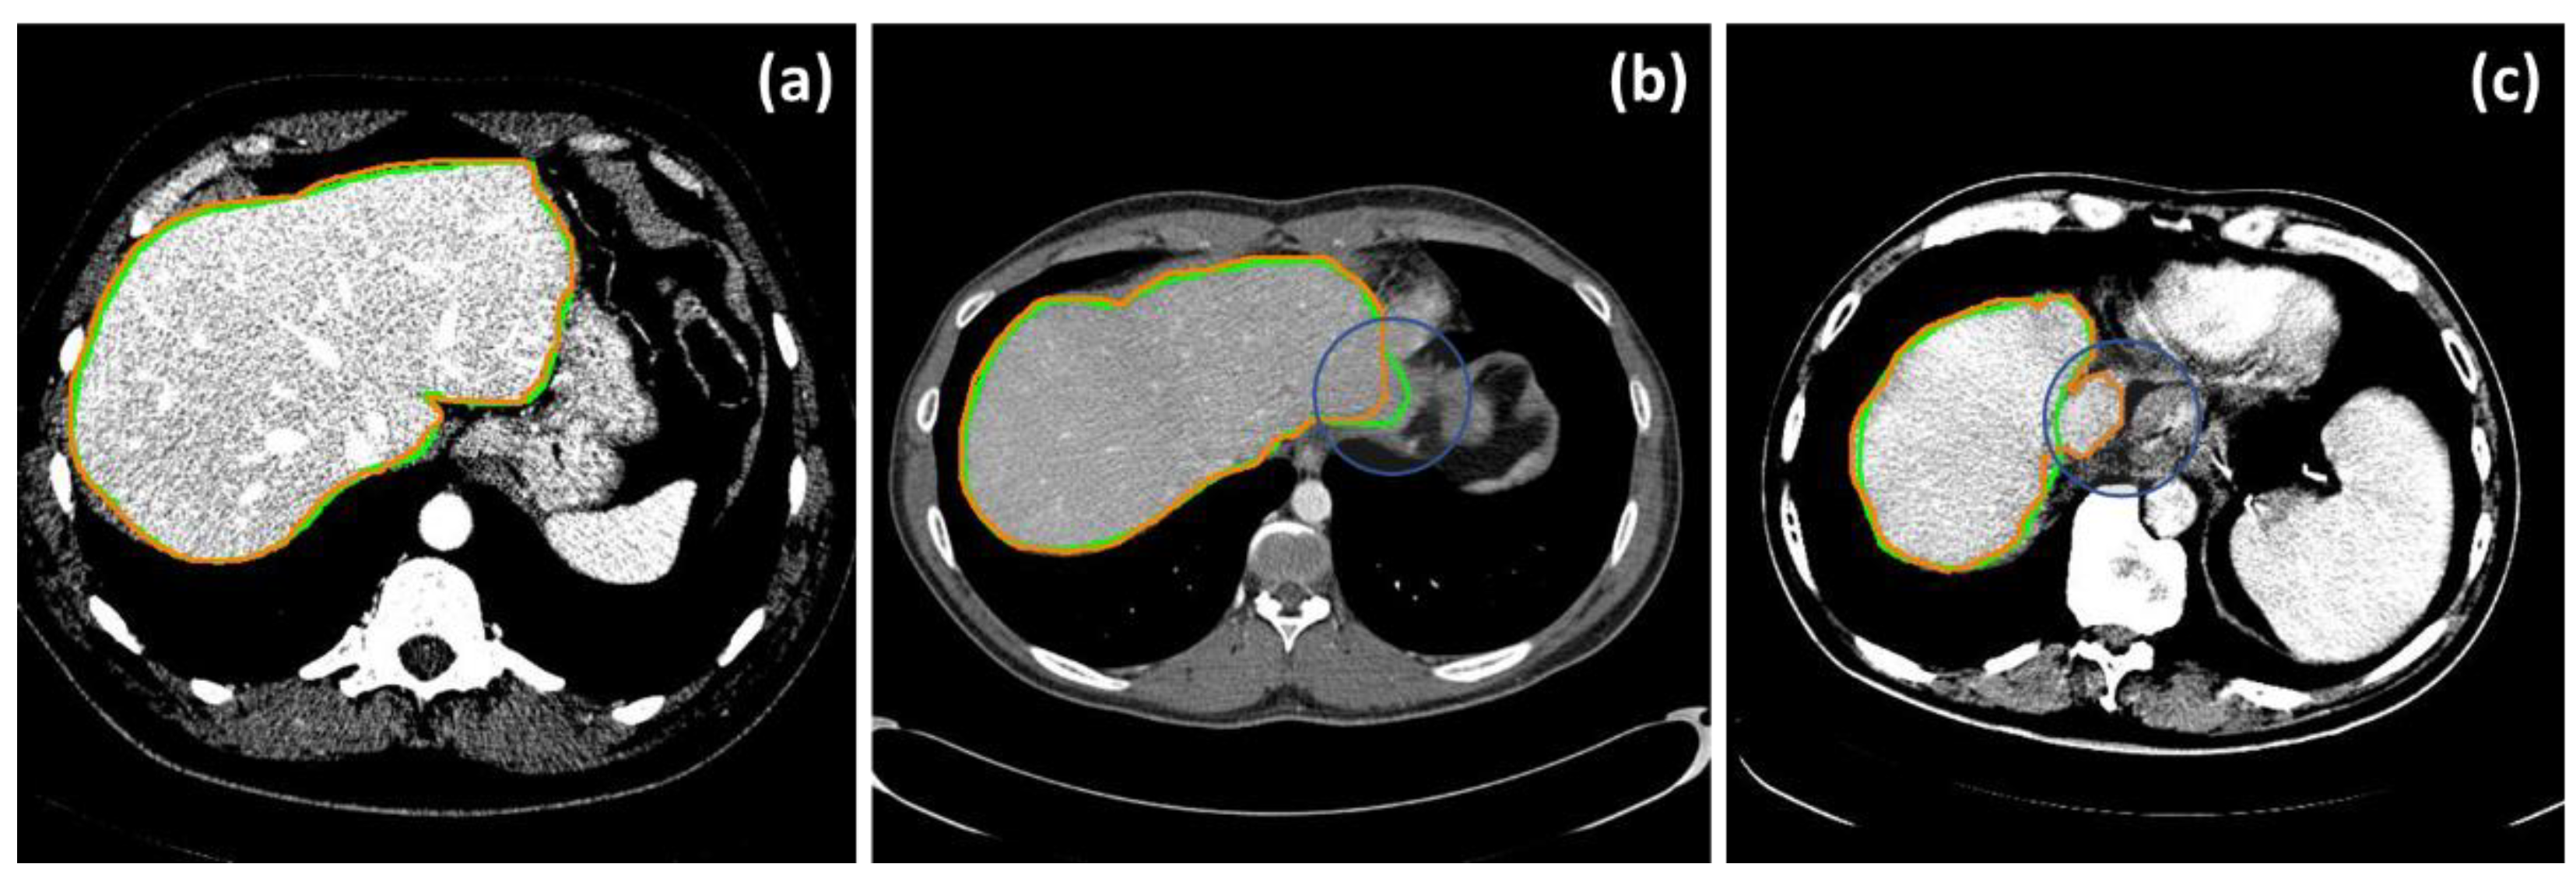

In addition to the numerical assessments, Figure 4 demonstrated selected instances of highly accurate (Figure 4a) and inaccurate results due, for example, to a low contrast boundary (Figure 4b), and mistakenly including the inferior vena cava (IVC) (Figure 4c), respectively.

Figure 4. Selected examples of accurate (a) and erroneous segmentation, due to an undefined boundary (b) and inclusion of the IVC (c). Green and orange contours are those of the ground truths and of the livers segmented by the proposed method, respectively.